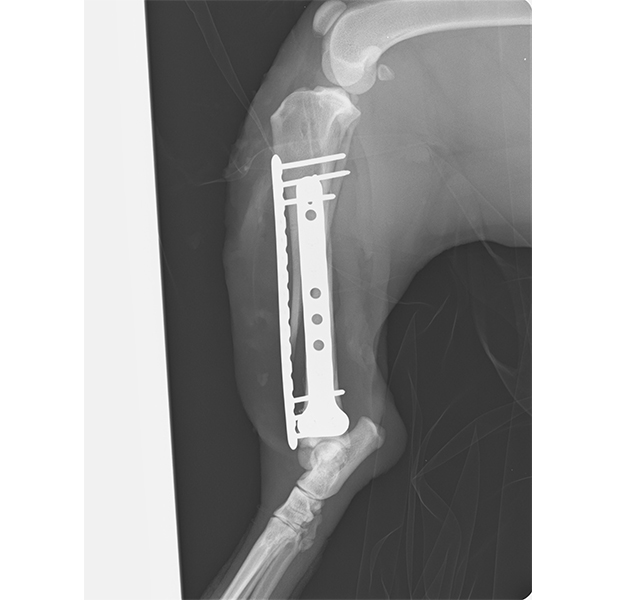

She had a very painful leg injury and needed urgent treatment in our veterinary hospital. X-rays revealed multiple fractures of her tibia and fibula (her bones between her knee and ankle). Poor Nakita underwent a tricky operation to allow her fragments of bone to heal. She has been recovering well at the RSPCA but is currently looking for a foster carer that can welcome her into their home while she continues her recovery.

Nakita just requires some crate rest and short leash walks in her temporary foster home while she overcomes her leg injury.

In a few more weeks, Nakita will have x-rays to monitor her recovery and slowly increase her exercise while she continues to heal.